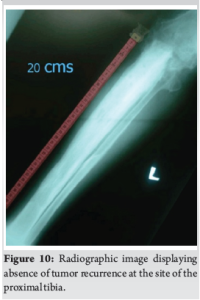

Arthrodesis was successfully achieved, and external fixator was subsequently removed. At 2 years follow-up, there were no signs of tumor recurrence. (Fig. 10).

In this case, despite the limitations, successful outcome was achieved with combination of tumor excision, Illizarov-assisted bone transport and arthrodesis with an iliac crest bone graft.